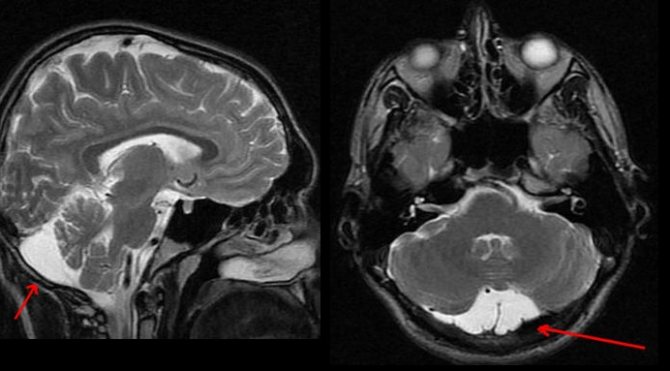

На сегодняшний день наиболее точным методом диагностики, позволяющим с высокой степенью точности отличить арахноидальную кисту от опухоли или гематомы, являются компьютерная томография (КТ) и магнито-резонансная томография (МРТ).

Несмотря на то, что КТ позволяет точно определить размеры и расположение кисты, наиболее точную и полную информацию об образовании дает МРТ. Обычно для диагностики арахноидальной кисты проводится МРТ-сканирование с введением в кровоток пациента контраста.

При этом опухоли мозга имеют свойство накапливать контраст, а кисты не впитывают его из кровеносных сосудов, что очень четко видно на МРТ.

Также МРТ-сканирование позволяет отличить кисту от кровоизлияний, гематом, гигром, абсцессов и других заболеваний со сходной симптоматикой. Кроме того, МРТ дает возможность выявить кисту даже в тех случаях, когда у пациента еще нет никаких проявлений, а сама киста имеет размеры всего в несколько миллиметров.